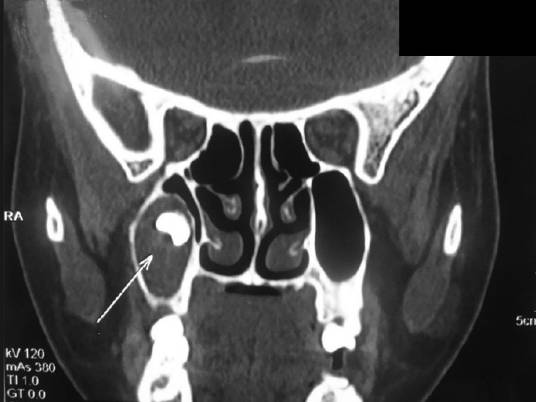

Диагноз устанавливается с помощью рентгеновского исследования. Для обнаружения кист используются такие диагностики:

- КТ (дает наиболее точные показания).